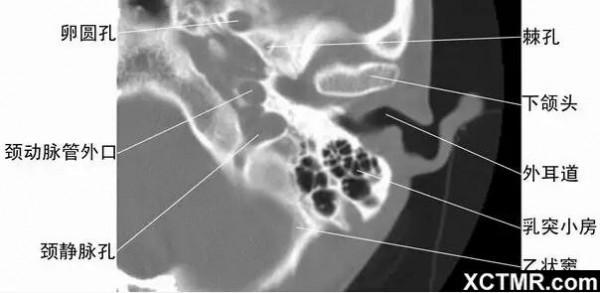

2耳部橫斷面-CT - 解剖圖片